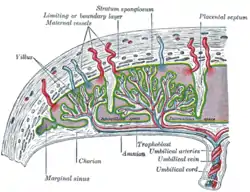

Sectional plan of the gravid uterus in the third and fourth month | |

The part of the decidua that interacts with the trophoblast is the decidua basalis (also called decidua placentalis), while the decidua capsularis grows over the embryo on the luminal side, enclosing it into the endometrium. The remainder of the decidua is termed the decidua parietalis or decidua vera, and it will fuse with the decidua capsularis by the fourth month of gestation.

Three morphologically distinct layers of the decidua basalis can then be described:

- Compact outer layer (stratum compactum)

- Intermediate layer (stratum spongiosum)

- Boundary layer adjacent to the myometrium (stratum basalis)

Within the decidua, occasional fibrinoid deposits form where the syncytiotrophoblast is damaged. The region of fibrinoid deposition where trophoblasts meet the compact portion of the decidua basalis is called Rohr's layer, while the fibrinoid deposits that occur between the compact and spongy layer of the decidua basalis is termed Nitabuch's layer (for Raissa Nitabuch). This layer is absent in placenta accreta.[2]